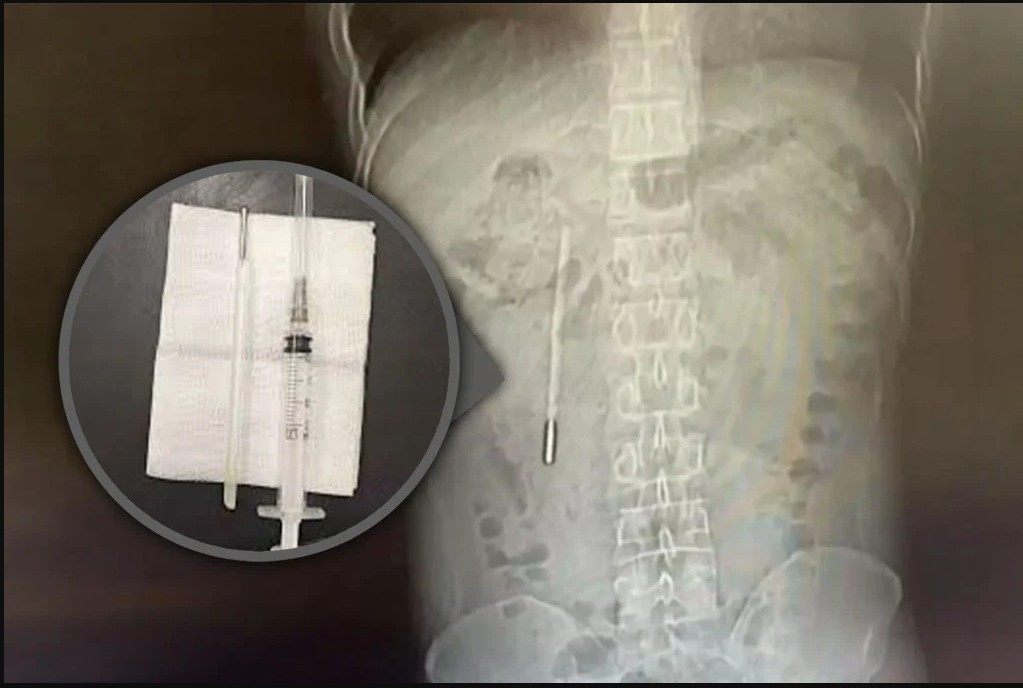

وكان الرجل، ويدعى وانغ، من مدينة ونتشو في مقاطعة تشجيانغ جنوب شرق الصين، قد خضع للعلاج في فرع لونغغانغ التابع للمستشفى الأول المرتبط بجامعة ونتشو الطبية. وكشف الفحص الطبي عن وجود جسم غريب في الاثني عشر، يُشتبه بشدة في أنه ميزان حرارة زئبقي، حيث كان الطرف المعدني يضغط مباشرة على جدار الأمعاء، ما شكّل خطرًا كبيرًا لاحتمال حدوث ثقب أو نزيف داخلي حاد.

وأفادت صحيفة «ساوث تشاينا مورنينغ بوست» أن العملية الجراحية كانت بالغة الدقة، نظرًا لبقاء الميزان داخل الجسم لفترة طويلة، وقربه من القنوات الصفراوية، ما زاد من خطورة التدخل الجراحي واحتمال إصابة جدار الأمعاء. ومع ذلك، تمكن الجراحون من إزالة الجسم الغريب خلال 20 دقيقة فقط، حيث ظهر «الترمومتر» سليمًا إلى حد كبير، رغم بهتان علامات القياس عليه، بحسب الصحيفة.